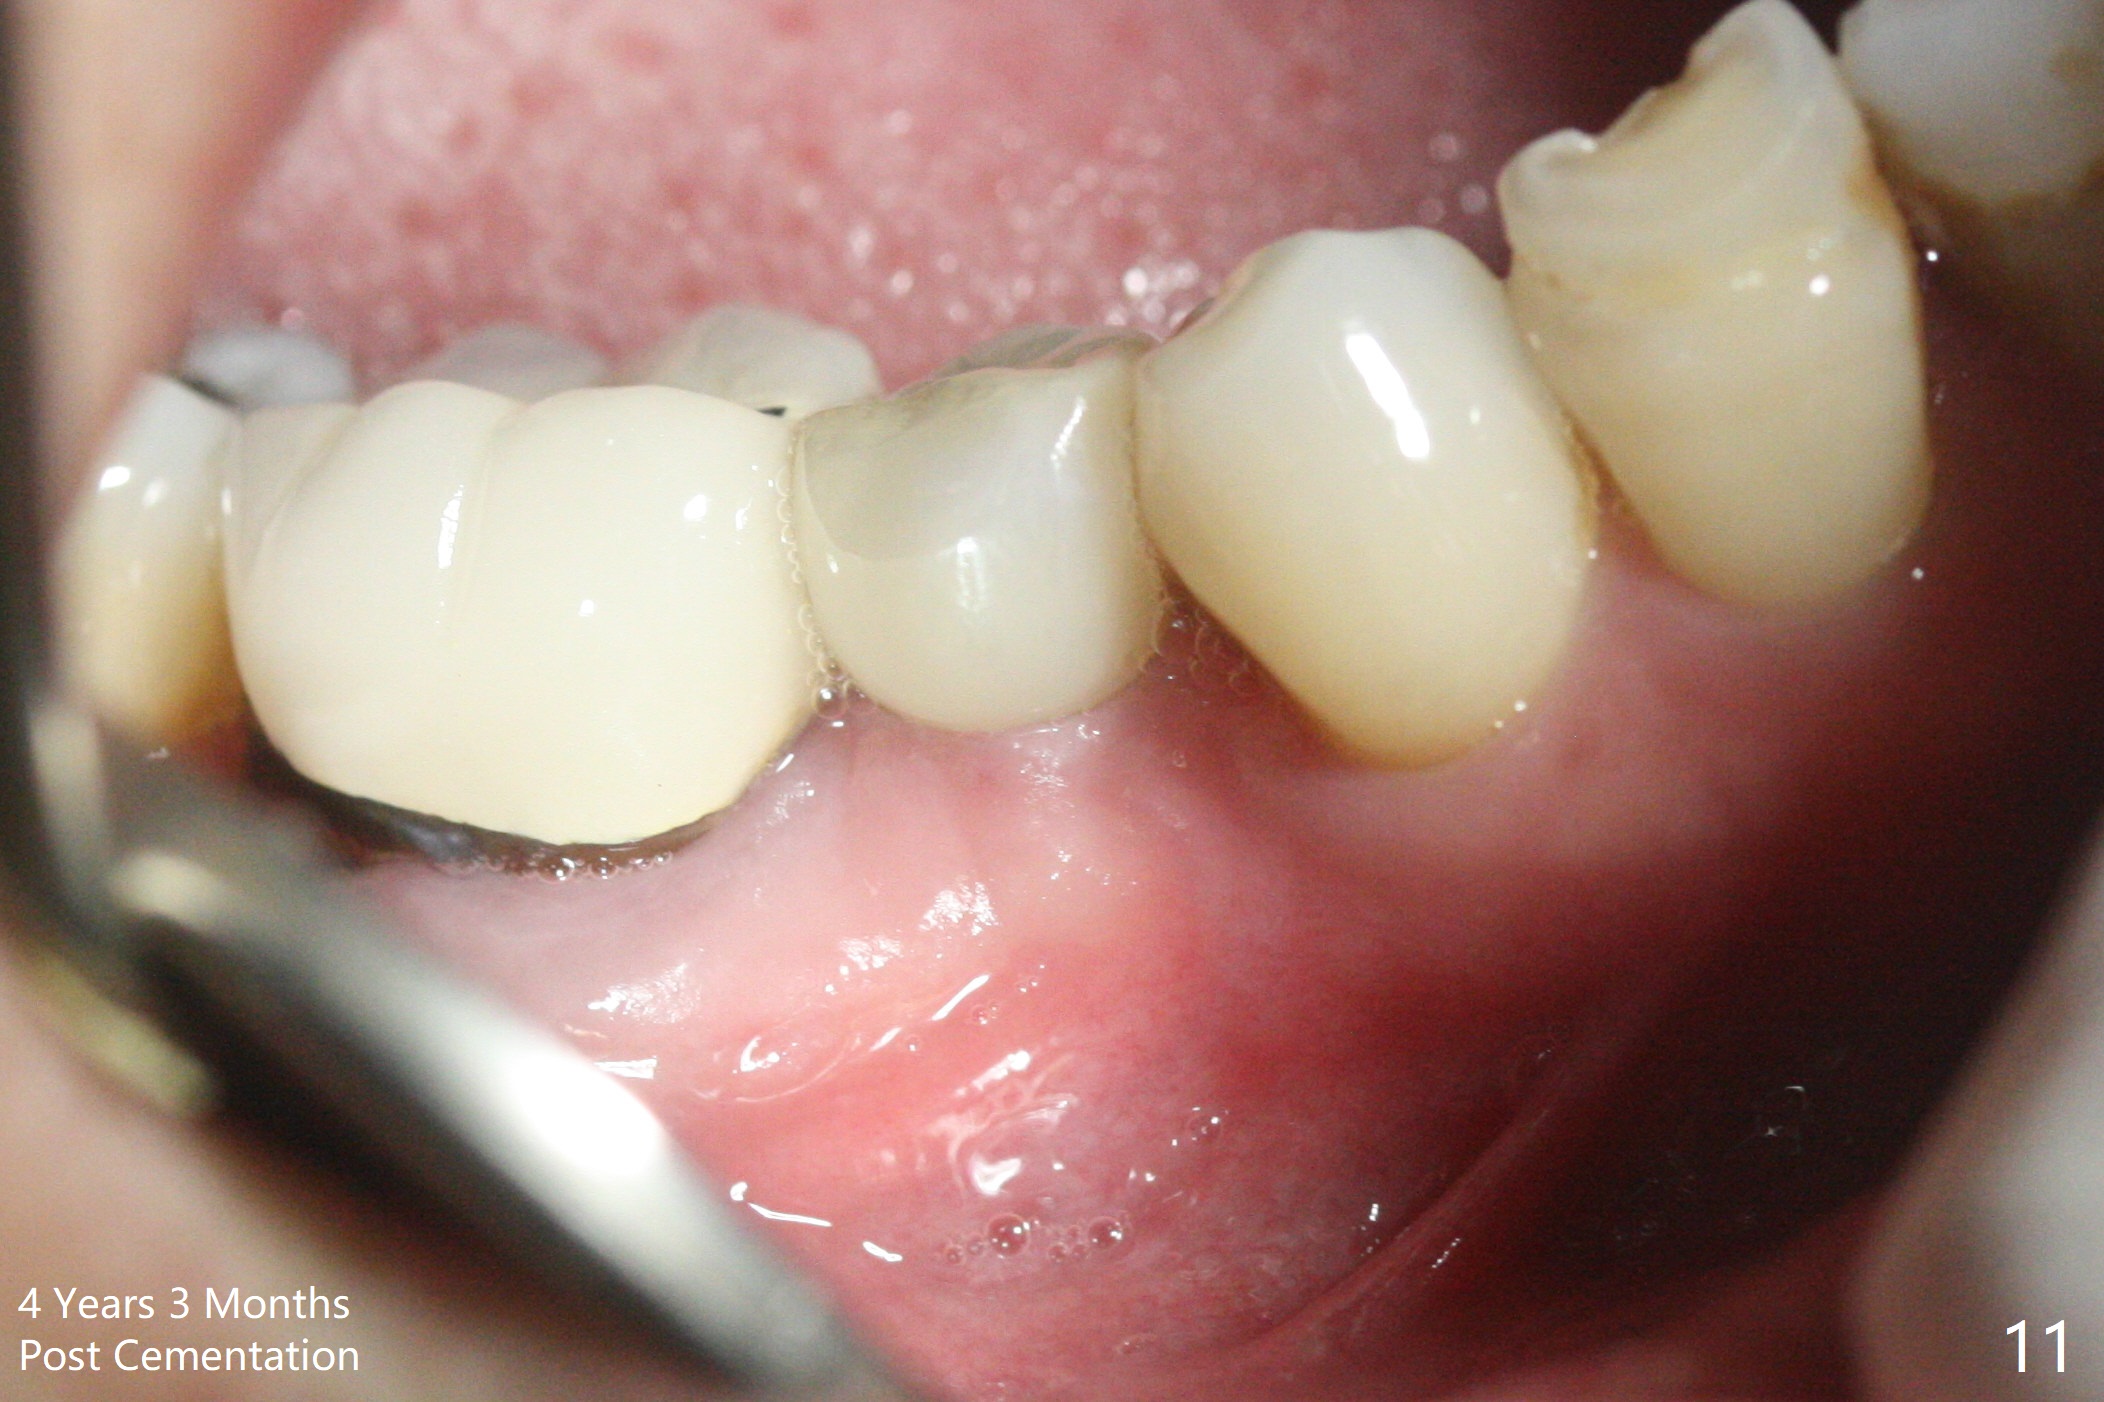

Preop photo shows the distal inclination of the tooth #28 (Fig.1). The distal surface of the latter is reduced before incision for implant placement at #29 (Fig.2). The buccolingual width is approximately 4 mm, as compared to 3 mm implant positioner (Fig.3). After 1.2x10 mm osteotomy (Fig.5), the mesiodistal cortical bone is removed with a small high-speed fissural bur (Fig.4). When a 2.5x12(2) mm 1-piece implant is placed (Fig.6), there is no buccal (Fig.7) or lingual plate perforation. There is no postop paresthesia. There is mild bone loss distal 4 months postop (Fig.8 *). Take photos before and after permanent crown cementation to show increase in ridge width after bone graft and improvement in gingival health after provisional modification. Take PA and/or BW post cementation to show that the distal bone resorption (Fig.8 *) is partially due to angulation. No continuous bone loss 15 months post cementation (Fig.9). There is mild bone resorption mesially 2 years 3 months post cementation (Fig.10). The soft and hard tissues remain healthy 4 years 3 months post cementation (Fig.11,12).